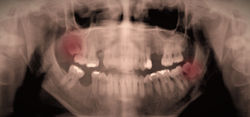

Dentes do Ciso